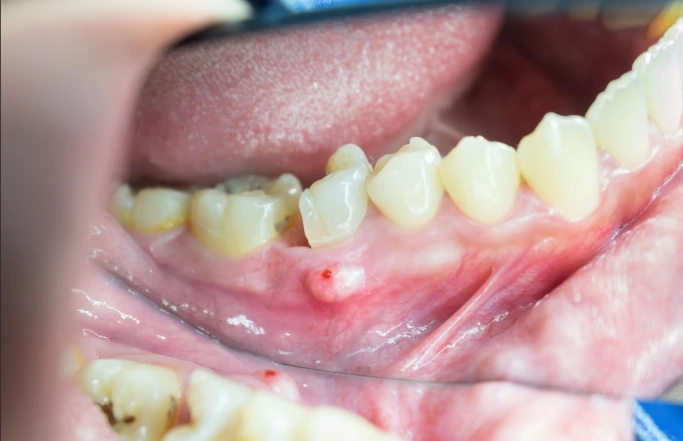

Then come the other guests to this unpleasant party. You might notice sudden sensitivity to hot and cold temperatures that lingers long after the source is gone. Your gums around the tooth may become red, swollen, and shiny. In some cases, the swelling can be significant, causing your face to look puffy on one side. You might even be able to see or feel a pimple-like bump on your gums near the root of the tooth – that's a draining fistula, and it's a classic sign of a tooth abscess trying to release pressure.

This is often the first in-office procedure to get immediate relief. The dentist makes a small cut in the gum to let the pus drain out. The pressure release is almost instant, and the pain drops dramatically. They'll then flush the area with a saline solution. Sometimes a small rubber drain is left in place for a day or two to ensure all the infection drains out.